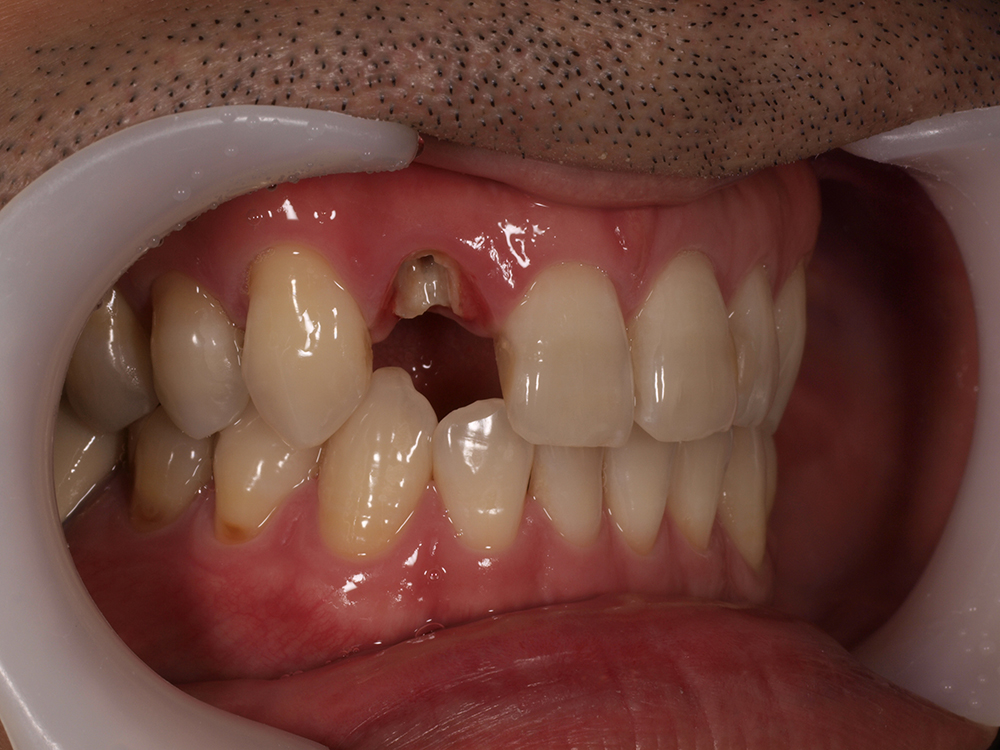

症例 インプラント

29歳 男性 歯科医療関係者紹介。また、お姉さんが歯科医療関係者。

- 主訴

- 左上1番目の歯が長期にわたり痛く、噛めない。

- 処置内容

-

1本インプラント埋入+再生療法。抜歯即時埋入、即時荷重法⇒抜歯を行い、

同時にインプラント埋入(即時埋入)、そして同時にインプラントへ仮歯を装着(即時荷重)

歯が無い期間なく、社会生活に支障が出ない

- 治療費用

- 約39万円(税込)

- 治療期間

9か月

手術当日に人工歯(仮歯)まで装着。 (通常待機期間は1年必要です。 (抜歯後6か月+インプラント(根)待機期間6か月+仮歯2か月))

- リスク

- 上部構造物、仮歯の破折、術後の腫れ(3日)、人工歯根脱落リスクがあります

- その他

- 学術雑誌、海外公演(アメリカ、ヨーロッパ)に多く紹介されたケース